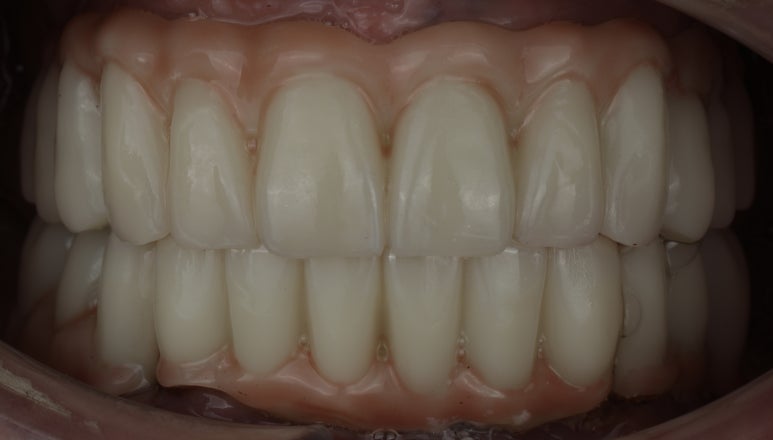

꼼꼼히 인상채득을 하고, 교합 고경을 체크한 후에, 환자분의 빠듯한 비행 스케줄을 맞추기 위해 단 5일만에 전악 임플란트 보철물이 완성이 되었답니다! ( 통상적으로는 7-14일이 소요됩니다 )

보철물 완성 후 안모 사진, 스트라우만 BLX 임플란트

남은 잔존치는 보철물을 올리면서 당일 발치후 최종 보철물 수복을 진행하였답니다.

15년은 젊어지신 모습에 저도 뿌듯했던 케이스 였답니다.

안면부 주름도 보철물 하나로 많이 개선되신 모습이죠?

정리하는 의미에서 전후 사진을 비교해 보았답니다.

안모상 주름 개선, 젊어보이는 효과 부여를 관찰할 수 있답니다.

전후 비교/ 중심선을 잘 맞출수 있었답니다.